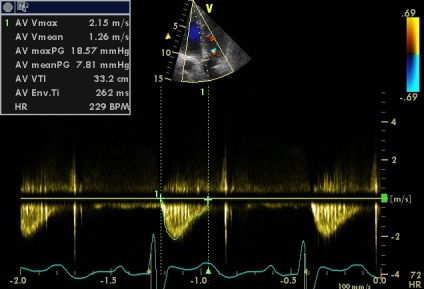

az aortabillentyű áramlási

2. fokozott gradiens aortabillentyű (18.57) és megközelítőleg azonos VTI LVOT VTI Ao és úgy kell értelmezni, egyszerűen következtében tachycardia?

2. megnövekedett gradiens aortabillentyű (18.57) és megközelítőleg azonos VTILVOTi VTIAosleduet értelmezni egyszerűen következtében tachycardia?

Tachycardia idején szkennelés nem (a klip jobb alsó sarkában a csatorna EKG monitorozás szívritmus alakzatnak, akkor változik a 73-77 perc). De érszűkület (akár minimális) szintén nem (igazad van), és enyhe növekedés sebessége és a színátmenet összefüggésbe hozható a megnövekedett perctérfogat (verőtérfogat LV). „Körülbelül egyenlő a VTI” csak beszélni a közelítő egyenlőség a terület és a terület AK BT LV (aorta regurgitatio nem számít, mert még kicsi, annak ellenére, hogy az alacsony PHT. Ebben az esetben a gyorsított összehangolás LZH- Ao nyomás nem jár gyors növekedése a diasztolés nyomás a bal kamrában, mint a súlyos aorta regurgitáció, és a gyors nyomás csökkenése az aortában miatt ürítőnyílás a sipoly).